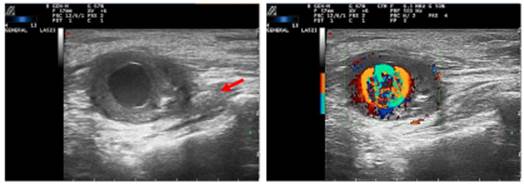

Ultrasound of the right elbow

Anechoic mass with thickened and hypoechoic walls, measuring 60 mm x 107 mm, dependent on the wall of the proximal ulnar artery, shortly after the bifurcation of the brachial artery, with intralesional power-Doppler signal, compatible with pseudoaneurysm vs. parietal aneurysm of the latter. In a position medial to the vascular lesion, the thickened median nerve is observed, with a diameter greater than 58 mm (Fig. 1).